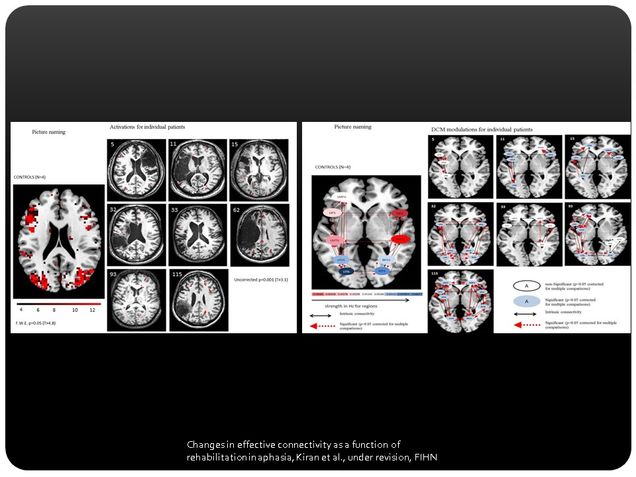

We are now interested in examining whether behavioral language recovery observed in treated patients is correlated with underlying functional changes in the brain as a result of treatment. Hence, we have started functional neuroimaging (fMRI) experiments to investigate activation in brain regions in patients with aphasia before and after they receive treatment.

It is hoped that changes in activation that are observed in the brain scans will provide us with some understanding of how language is recovered in the damaged brain following treatment. This important data will contribute to the growing body of evidence supporting the notion of brain plasticity in adulthood and after brain damage.

Kiran S, Meier EL, Kapse KJ and Glynn PA (2015) Changes in task-based effective connectivity in language networks following rehabilitation in post-stroke patients with aphasia.Frontiers in Human Neuroscience. 9:316. doi: 10.3389/fnhum.2015.00316